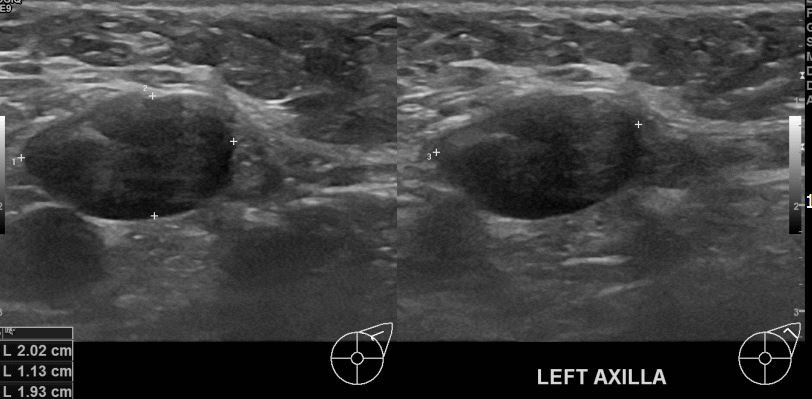

좌측겨드랑이에 만져지는 멍울있어 내원하신 50대 여성분으로 조직검사후

유방암 진단되었읍니다